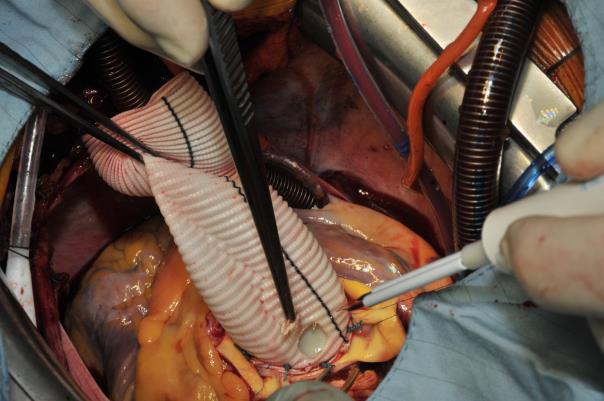

Thereafter, the work is continued at the aortic root. The anastomoses of the coronary orifices with the vascular graft are then performed. First a neo-ostium has to be created using a thermal cutter (Image 4). The author always begins with the left coronary artery re-attachment. This anastomosis is performed using a continuous 6.0 Prolene suture. A bovine pericardial strip is used only exceptionally in case of very friable coronary buttons or in case of aortic dissection. For the left-handed surgeon, it is rather easy to start this continuous suture from inside the coronary orifice and then from outside of the graft. The posterior part of the anastomosis is constructed and then the suture is changed. For the anterior part of this anastomosis, the suture is stitched from outside of the coronary orifice to inside-out of the vascular prosthesis (Image 5). When the left coronary orifice has been re-implanted, the same procedure is done for the right coronary artery and the anastomosis is performed in the similar way as the left side (Image 6): here the suture is stitched (for the back wall) from inside-out of the graft and thereafter from outside - in. Once both coronary anastomoses have been performed, the graft is pressurized using cold blood cardioplegia into the aortic root and cross-clamp for the graft. At this stage, some fibrin glue may be used to seal the small suture line.

Image 4: Creation of the left neo-orifice to reattach the left coronary artery, using a thermal cutter.

At this stage, the ascending aorta is de-aired using a needle and the cross-clamp is removed. The patient is still in Trendelenburg position and the de-airing is facilitated with the use of CO2 insufflation in the operating field (Image 7). Epicardial pacemaker electrodes are placed on the ventricle and the right atrium and the patient is weaned from cardio-pulmonary bypass under AAI-stimulation 90/min. as soon as the core temperature has reached 35.5 °C.

Image 7: ;Intraoperative situs at the end of the procedure. The composite graft prosthesis has been anastomosed with the proximal arch – ascending graft. A needle is used for de-airing. The patient is in Trendelenburg position. Left the anteflow side-arm with the arterial cannula for return from CPB.